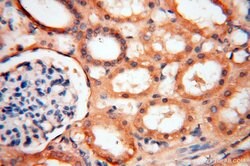

SYK Rabbit anti-Human, Mouse, Rat, Polyclonal, Proteintech

This gene encodes a member of the family of non-receptor type Tyr protein kinases. This protein is widely expressed in hematopoietic cells and is involved in coupling activated immunoreceptors to downstream signaling events that mediate diverse cellular responses, including proliferation, differentiation, and phagocytosis. It is thought to be a modulator of epithelial cell growth and a potential tumor suppressor in human breast carcinomas. Alternatively spliced transcript variants encoding different isoforms have been found for this gene.Specifications

| Immunohistochemistry (Paraffin) | |

| Human, Mouse, Rat | |